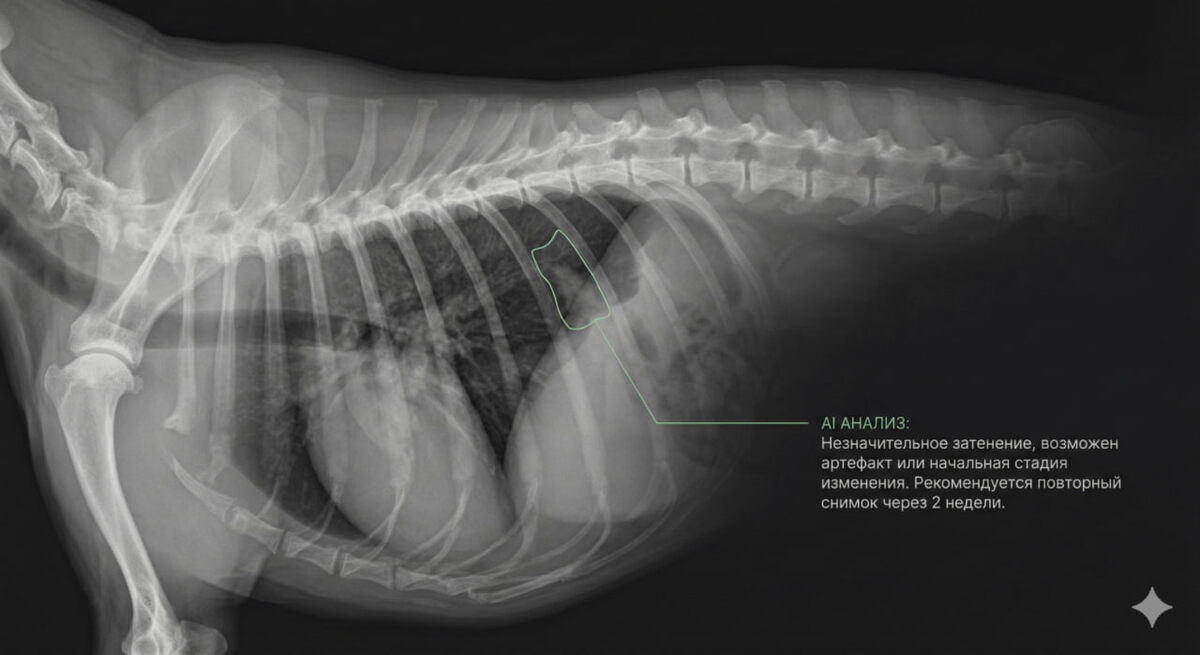

Респираторные заболевания у собак и кошек нередко диагностируются на основании аускультации и рентгенографии, а значит, во многом зависят от субъективной оценки ветеринарного врача. Международная группа исследователей проанализировала, насколько методы искусственного интеллекта уже сегодня способны повысить точность такой диагностики. В исследованиях, где использовался аудиоанализ, алгоритмы применяли для выявления синдрома обструкции дыхательных путей у брахицефалических пород и других патологических дыхательных шумов. В отдельных работах точность классификации достигала 90%. Источник.